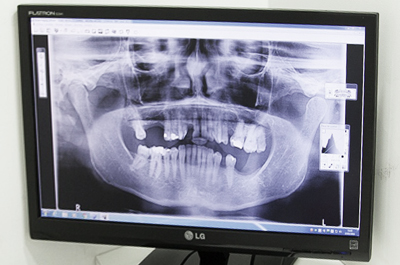

환자 상태 파악

치아, 뼈는 물론 당뇨, 고혈압 등

건강상태 전반 파악

3D CT등 정밀진단을 바탕으로

수술 계획 및 진행